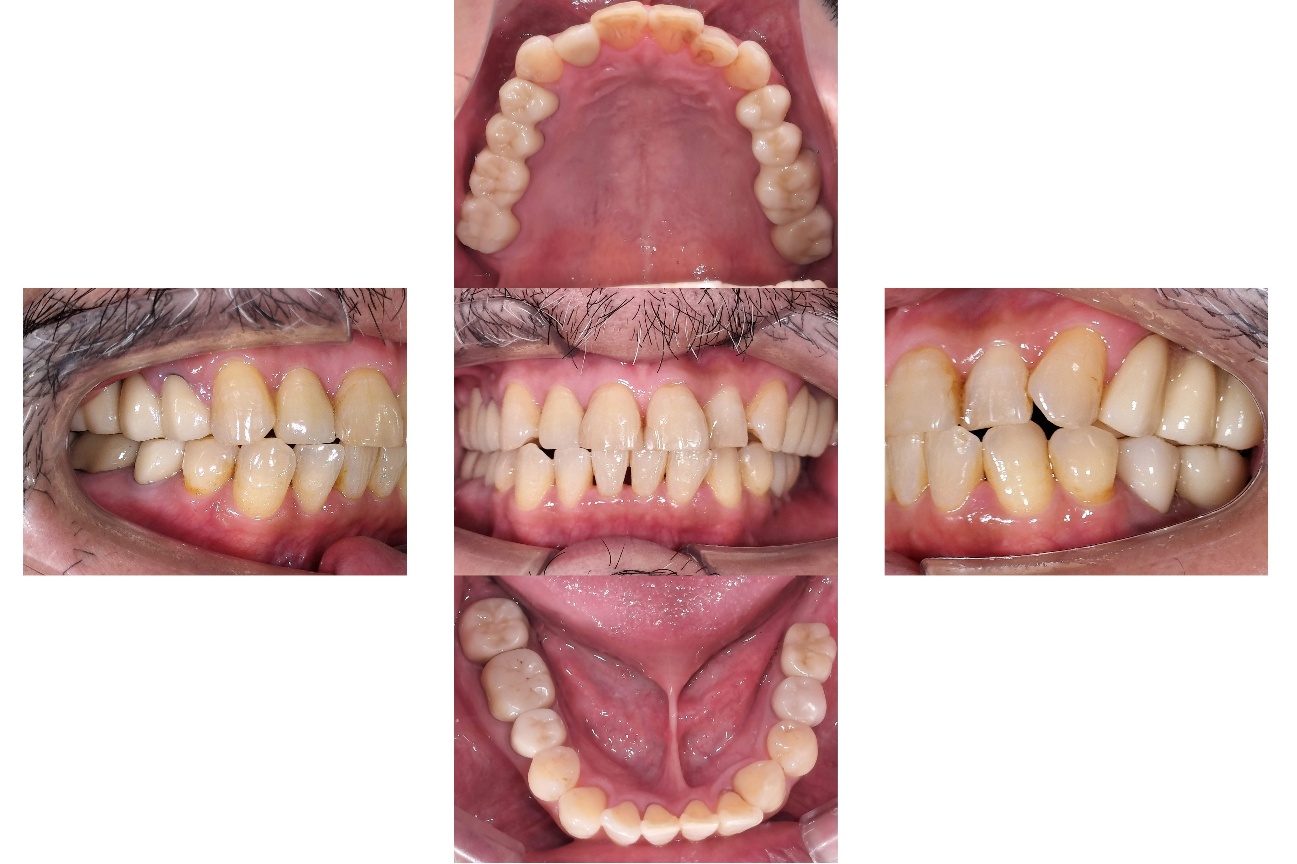

前歯の見た目と噛み合わせのバランスを整えたケース

「前歯が強くかみ込んでいる気がする」「歯並びだけでなく、噛み合わせも気になる」

このようなお悩みでご相談いただくことがあります。

今回の患者様は、ディープバイト(過蓋咬合)による前歯の見た目と噛み合わせを気にされて来院されました。ディープバイトとは、上の前歯が下の前歯に深く重なっている噛み合わせのことで、見た目の問題だけでなく、前歯や顎への負担につながることがあります。

本症例では、マウスピース型矯正装置(インビザライン)を用いて治療を行いました。合計84枚のアライナーを使用し、歯並びだけでなく咬合の深さにも配慮しながら治療を進めました。

治療後は、前歯の見た目のバランスが整い、噛み合わせも改善しました。

当院では、見た目を整えるだけではなく、治療後の噛み合わせまで考慮した矯正治療を大切にしています。